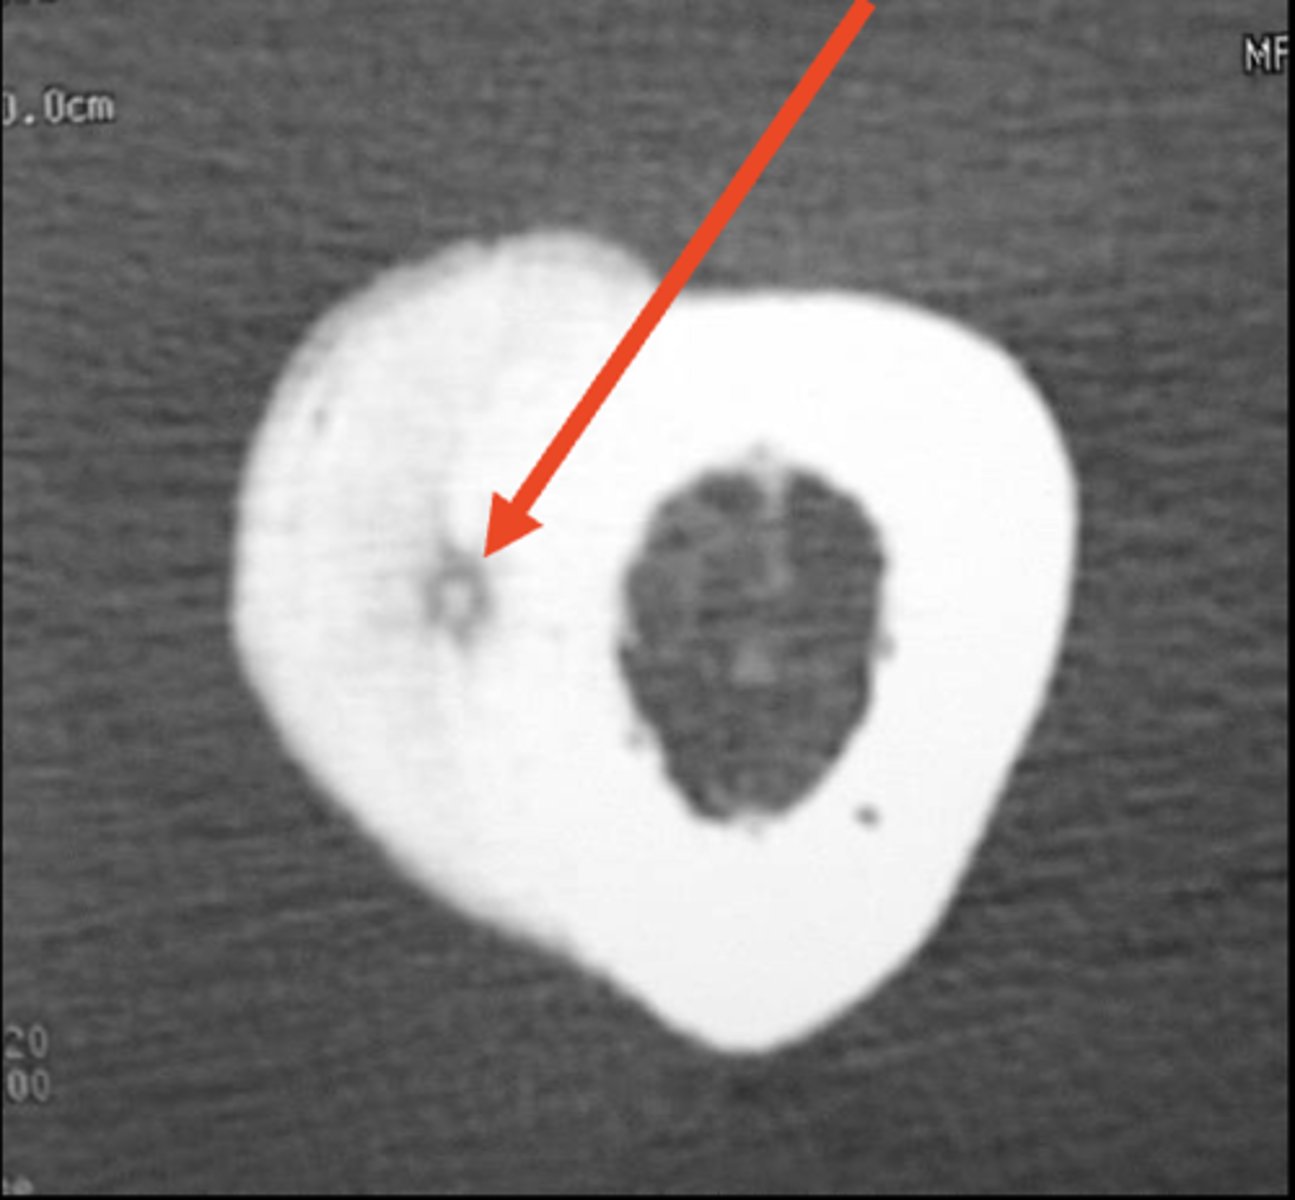

Fluid-Fluid Levels

- Most compatible with aneurysmal bone cyst

- Also seen in giant cell tumors, simple bone cysts, and telangiectatic osteosarcoma